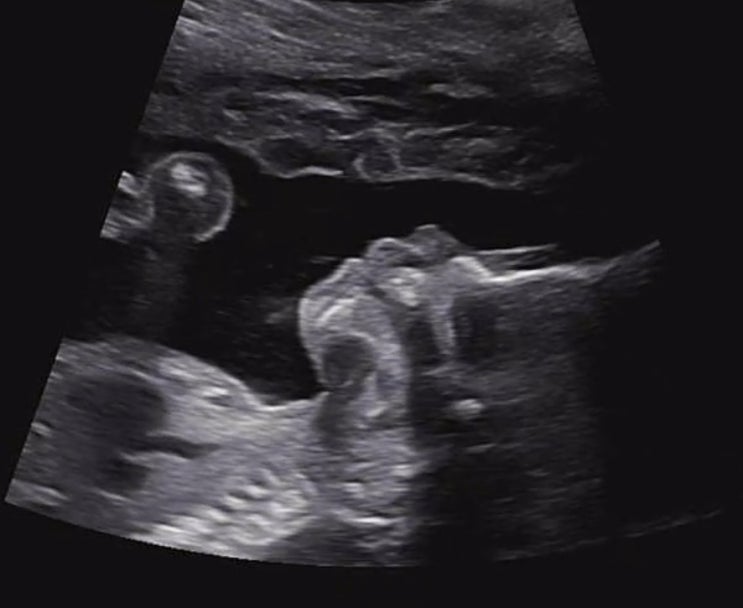

임신기록 ? (17주 ~21주 )

결혼기념일에 받은 문자 튼튼보이 굿보이 건강하게 나와랏? 16주차에 정기진료 보러 갔을때 태반이 경부...